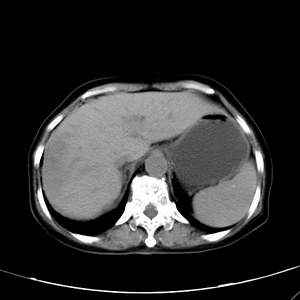

患者,女性,77岁,右上腹胀痛月余。afp正常。ca125升高。即往无肝炎病史。

肝右叶病灶是胆管细胞癌吗?门静脉右支癌栓形成?右侧肾上腺有问题吗?

肾上腺应该问题不大,肾上腺的大小和形态在临床上差异很大,所以大小无实际意义

最后5幅图片是延时7分钟的。门静脉右前支内有充缺吗?如有,肝血管瘤不好解释。

病灶渐进性向心性强化,延时病灶中心见条片状高密度影,局部见肝包膜回缩征,结合病人无肝炎病史,考虑肝右叶胆管细胞癌,门脉右支癌栓形成。